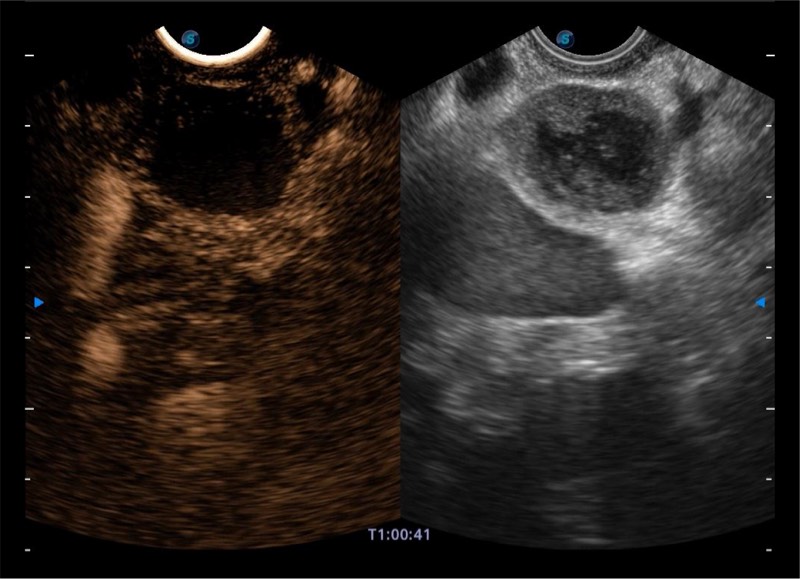

• 搭载百万级CMOS成像技术

• 及自主研发凸阵换能器,

• 可呈现优质的内镜和超声画面

基于二十年的超声技术积累,db真人体育官网提供了最新一代的独立超声主机,在提供高质量图像的同时满足多学科使用。具备常见多普勒技术并提供弹性成像、声学造影等高端影像技术。新一代传感器具有更强的抗干扰能力并减少图像伪影。

• 150°超声扫描角度

• 4-12MHZ宽频输出